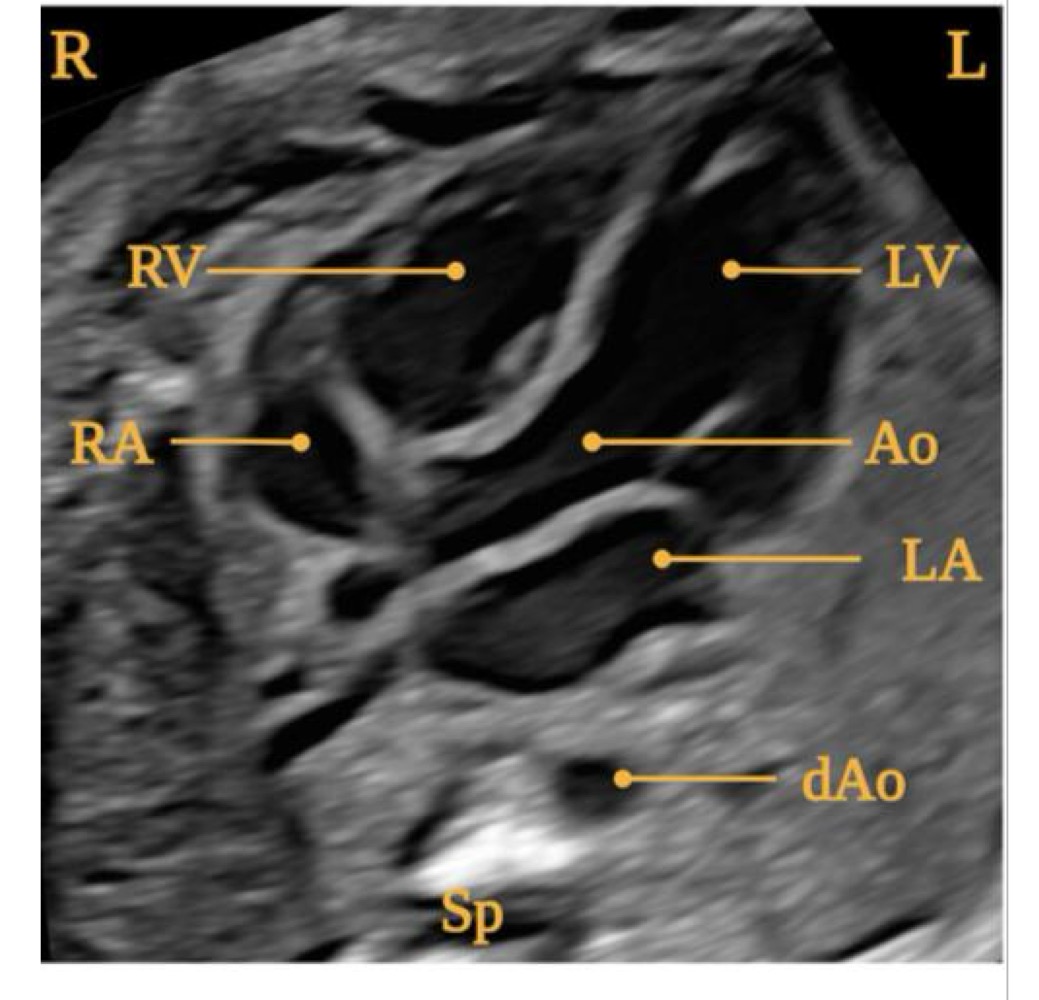

Right ventricle

Left ventricle

Right atrium

Aorta

Left atrium

Descending aorta